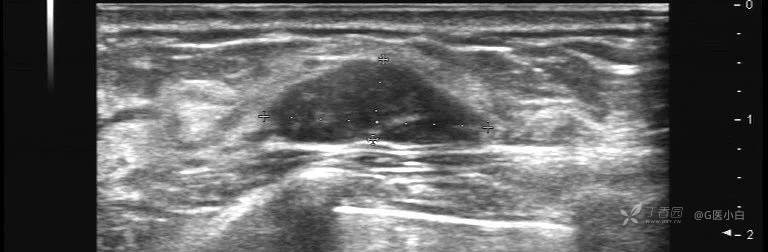

◆边缘清晰、卵圆形、平行于皮肤、回声低于脂肪、无后方回声改变或后方回声轻度增强的实性肿块。

对于这类结节的处理意见是:6、12、24个月随访,若随访过程中出现以下变化可以重新评估分类:

①随访过程中,肿块大小缩小,可降为2类

②随访过程中,肿块消失,可降为1类

③随访过程中,肿块直径增大超过20%或有其他可疑改变,则应调整为4类,建议活检